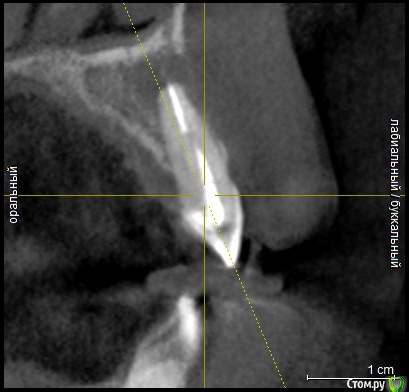

Ankazabolevshaya Опубликовано 28 мая, 2016 Поделиться Опубликовано 28 мая, 2016 Здравствуйте, уважаемые врачи! Очень сильно нуждаюсь в вашей помощи. В 2013 мне лечили два передних зуба (клык и передний). Пломбировали каналы, но коронки не ставили. Этой зимой я почувствовала боль в передних зубах в районе челюсти. Раздражение в дёснах. Резь. Потом вылез какой-то пупырь на десне. Я думала, что это стоматит. Не верила тем, кто мне говорил про нужность обзорного снимка. Признаю свою глупость. Теперь, после КТ оказалось что у меня сломаны эти каналы, а под левым клыком пустота. А пупырь, как мне сказали - это выход свища.Мне предложили зуб удалять. Как-то восстанавливать эту пустоту. Потом делать имплантацию. Есть ли сегодня технологии, позволяющие восстанавливать это пространство под зубом без его удаления, с последующей коронкой на него? И ещё один вопрос: могло ли все это случится из-за какой-нибудь заразы, занесенной во время лечения этих двух зубов в 2013г. ? Так же был момент ранения слизистой левой ноздри, как раз над свищем, который на десне. Просто очень часто слизистая иссыхала в одном месте и я травмировала слизистую. Буду очень благодарна за ответ. От меня в клинике ждут решения, а я переживаю, что улыбка испортится с искусственным зубом. Зуб этот свой очень люблю. Анна. Ссылка на комментарий

Ankazabolevshaya Опубликовано 28 мая, 2016 Автор Поделиться Опубликовано 28 мая, 2016 если судить только по снимкам, то даа скажите, как по Вашему, это киста прикорневая? Или челюсть разрушена? Нужно восстановление челюсти? Ссылка на комментарий

red_butler Опубликовано 29 мая, 2016 Поделиться Опубликовано 29 мая, 2016 а скажите, как по Вашему, это киста прикорневая? Или челюсть разрушена? Нужно восстановление челюсти? это не важно и корень ведь сломан, поставить под коронки всё равно можно? перелома не увидел И еще последнее, как Вы относитесь к процедуре - депофорез? В моём случае стоит в эту торону смотреть? бесполезно 2 Ссылка на комментарий

Ankazabolevshaya Опубликовано 29 июня, 2016 Автор Поделиться Опубликовано 29 июня, 2016 Здравствуйте! Сегодня вновь была у стоматолога. Ситуация такая (очень нехорошая): После того, как заложили лекарство - свищ так и не закрылся. Доктор очень удивился. Вновь заложил лекарство, но уже добавив какой-то йодсодержащий препарат. А затем сделал снимок (мне его не дал, поэтому собираюсь сделать кт снова). Рассматривая снимок, он очень сильно огорчился (даже оплату не взял за посещение). Сказал, что раньше через микроскоп ситуацию не увидел такой, какая она скорее всего является. Что это очень может быть - резорбция корня и скорее всего внутренняя. Что то, что мы сейчас сделали скорее всего не принесёт результата. И что если даже затянется свищ, хорошего всё равно мало...Отсечение корня не поможет – расстояния там какие-то маленькие, зуб упадёт от яблока...Доктор говорил про то, что можно чем-то залить, про штифт… не успевала фиксировать эти предположения и не смогла запомнить формулировки. Может быть всё зря? Или всё же стоит идти дальше? Доктор хороший, один из лучших в городе. Снимок после последних процедур постараюсь сделать и выложить побыстрее. Ссылка на комментарий